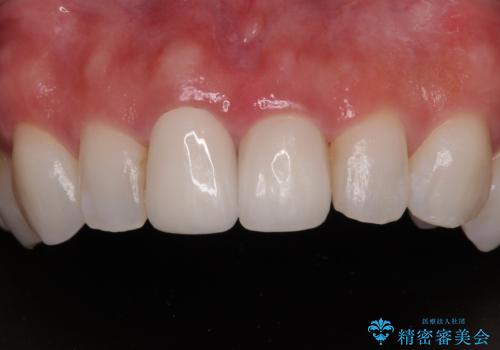

拡大鏡視野下で、被せもの、金属の土台、虫歯を除去し、ファイバーの土台(ファイバーコア)をたてて、オールセラミッククラウンに適した形に整えました。

患者様のご希望で周りの歯も白くしたいとのことでオフィスホワイトニング、ホームホワイトニングで色の調整を行い、色味が落ち着いてから、歯と歯茎の間に圧排糸と呼ばれる糸を入れてシリコーン印象を行いました。

見た目と機能面ともに満足していただきました。

今後はメンテナンスで通ってもらいながら、ご希望であればホームホワイトニング、オフィスホワイトニングを行っていく予定です。